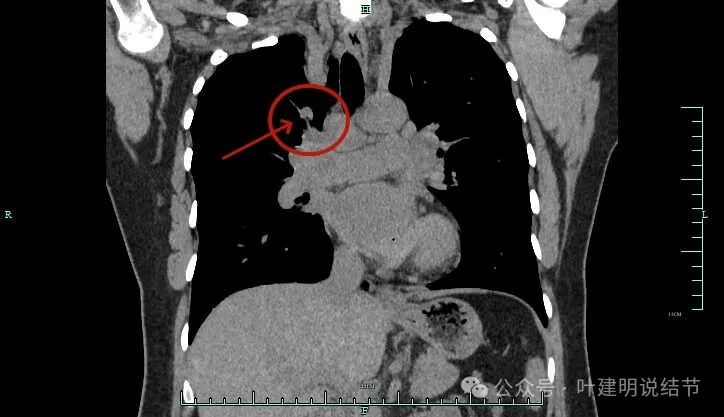

冠状位主病灶结节状,有血管贴边,恶性不能除外。

隆突下明显肿大淋巴结

左侧肺门与纵隔肿大淋巴结

左侧肺门处淋巴结肿大明显。

双侧肺门与纵隔明显肿大淋巴结。

右侧腔静脉旁肿大淋巴结。

下肺静脉旁肿大淋巴结。

肺门部明显肿大淋巴结。

右侧肺门与纵隔肿大淋巴结